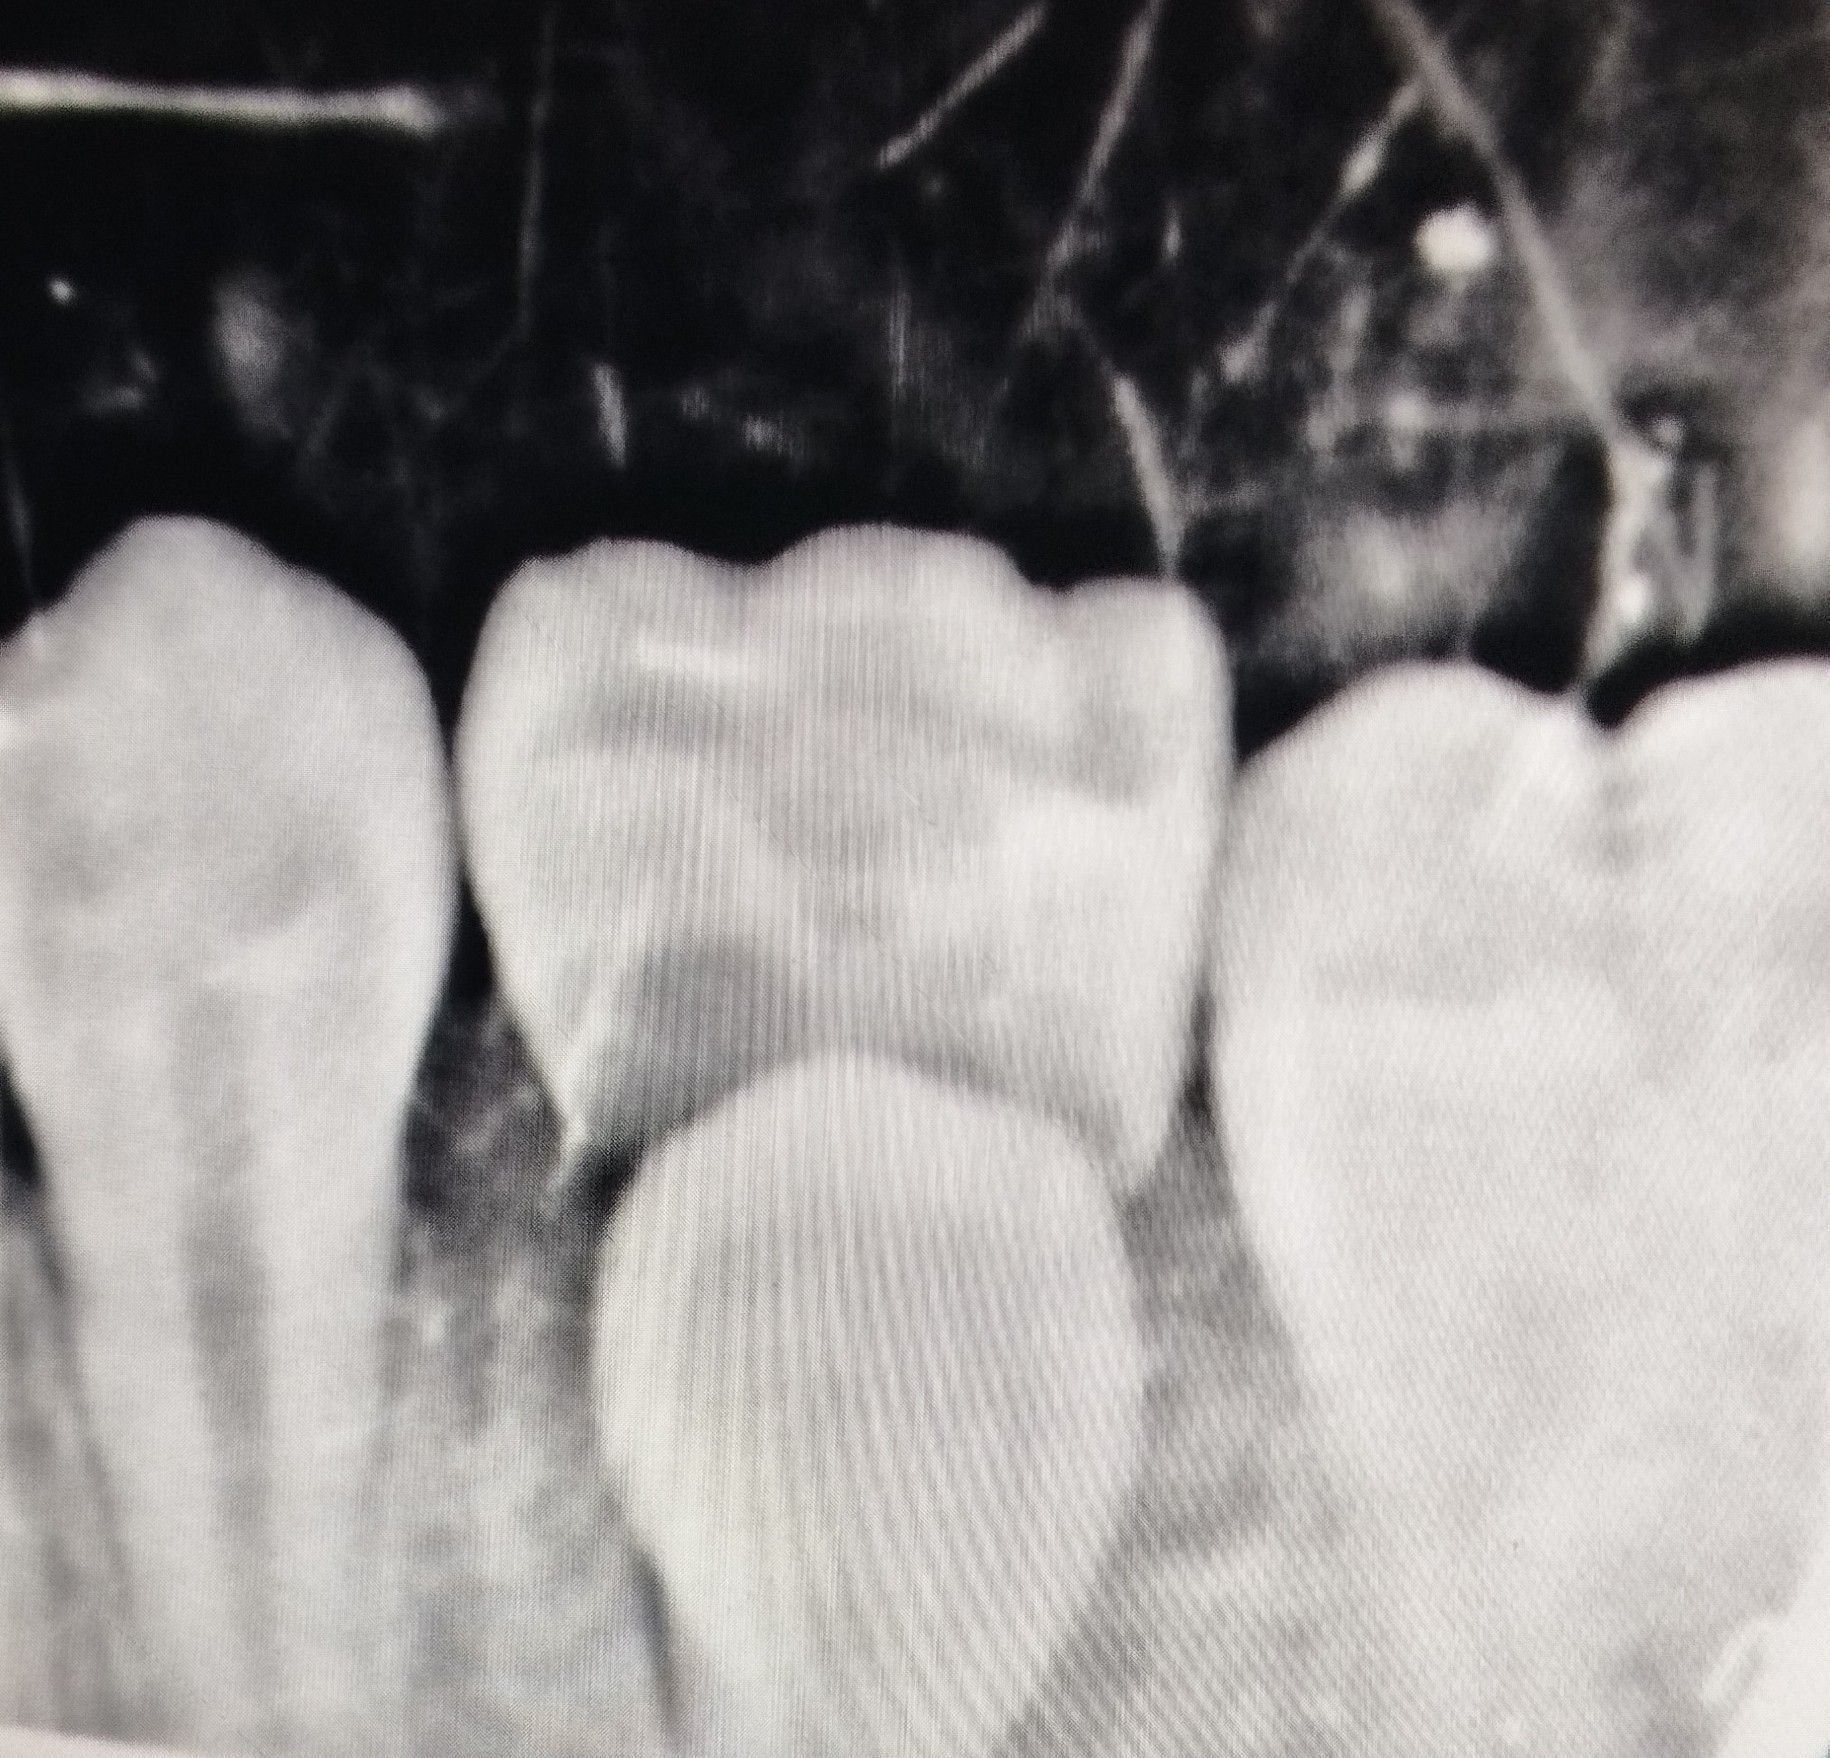

Identify the Erupting Tooth

Identify the erupting tooth in the x-ray above.